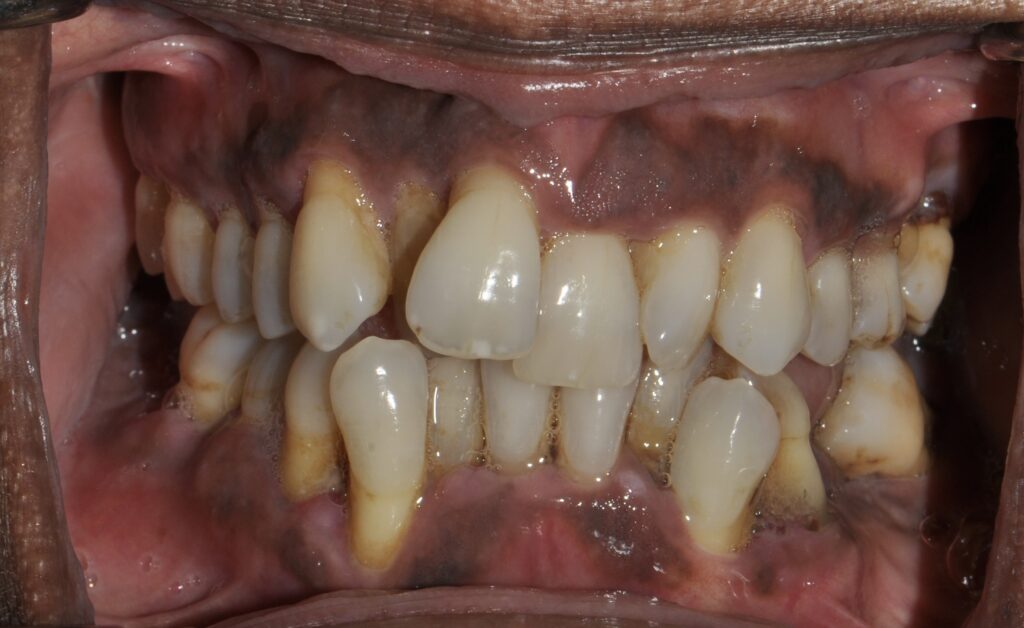

Ortho Before & After

Pre-ortho to Post-ortho with implant #7 and veneer #10

Pre-Treatment and Post-Treatment